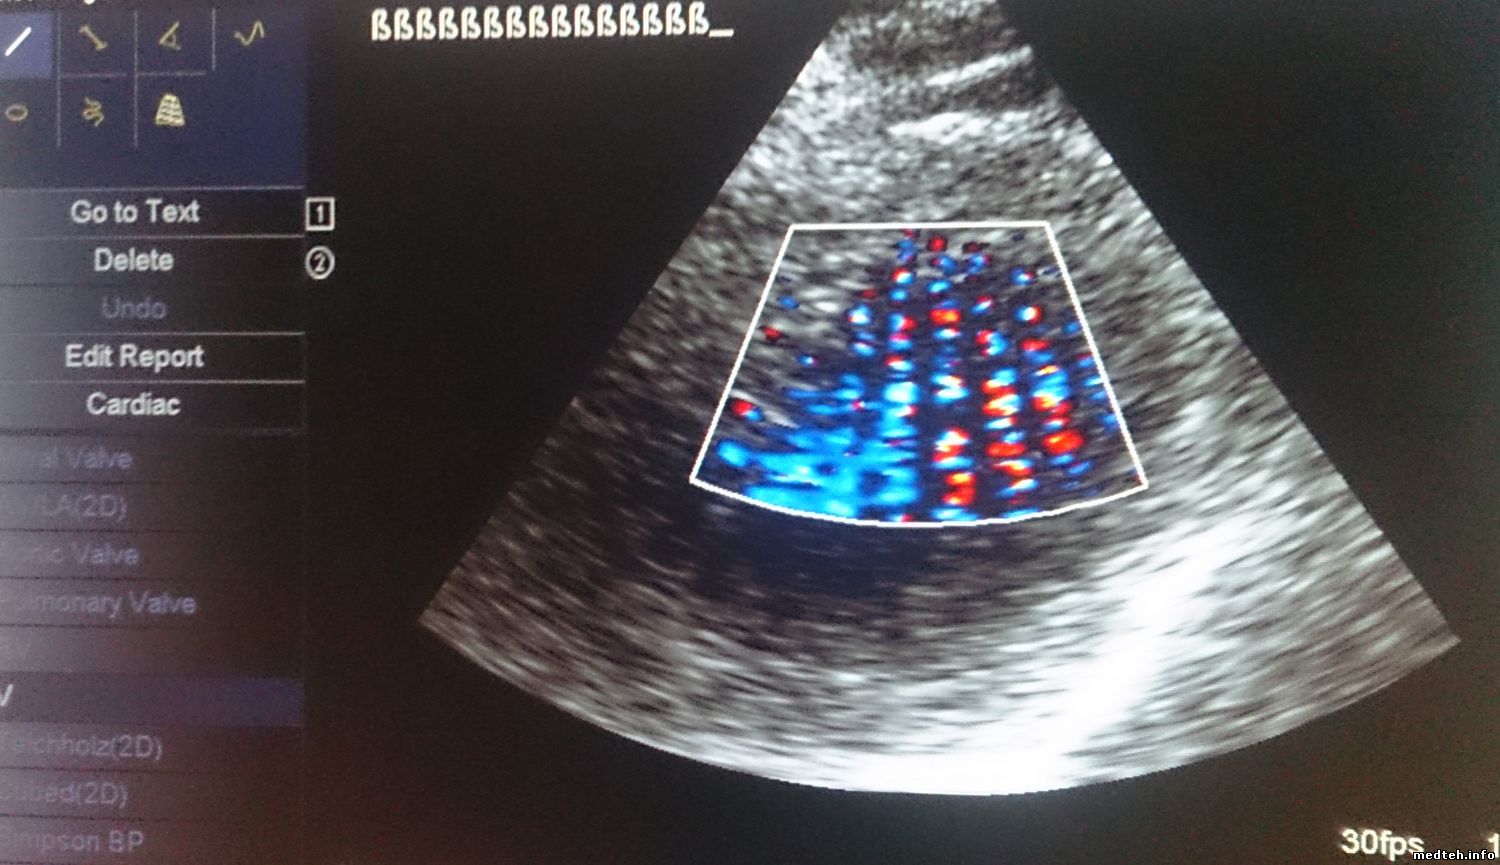

Сразу после включения качество более-менее (рис.1), хотя заметно, что изображение немного "восковое". К концу рабочего дня изображение ухудшается, повышается шум, изображение "плывет" (рис.2,3). На всех датчиках, хуже всего на фазированном. Появилось это давно. Аппарат ремонтировали по гарантии несколько лет назад, что-то меняли. Делали-ли tune-up, неизвестно. Пароля, естественно, нет. Как проконтролировать напряжения? Какие тесты можно сделать?